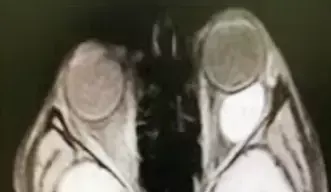

Рисунок 6. МРТ глазных орбит с контрастированием. На фоне проводимой терапии состояние без динамики, в связи с чем проведено дообследование: КТ орбит и МРТ орбит с контрастом. КТ показало образование левой орбиты, активно накапливающее контрастное вещество. МРТ орбит с контрастом — образование левой орбиты 2,6×1,5×2,9 см, активно накапливающее парамагнетик (см. рис. 6).

— На МРТ мы видим образование, которое находится под верхней стенкой глазницы, тесно примыкает к глазному яблоку и мышцам (см. рис. 10). Проводим трансконъюнктивальную орбитотомию и выделяем образование, тесно связанное с верхней косой мышцей (см. рис. 11). К сожалению, ее при выделении образования приходится пересечь. Иммуногистохимическое исследование подтверждает эмбриональную рабдомиосаркому, — рассказывает офтальмохирург. — Пациент продолжил лечение у онкологов. На данный момент он в ремиссии уже 3 года. Мы прооперировали его по поводу вертикального непостоянного косоглазия, которое развилось вследствие того, что мы резицировали часть верхней косой мышцы.